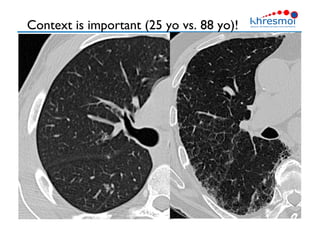

Context is important (25 yo vs. 88 yo)!

•  Images out of their context

loose most of their sense

Context is important(25 yo vs. 88 yo)! 26